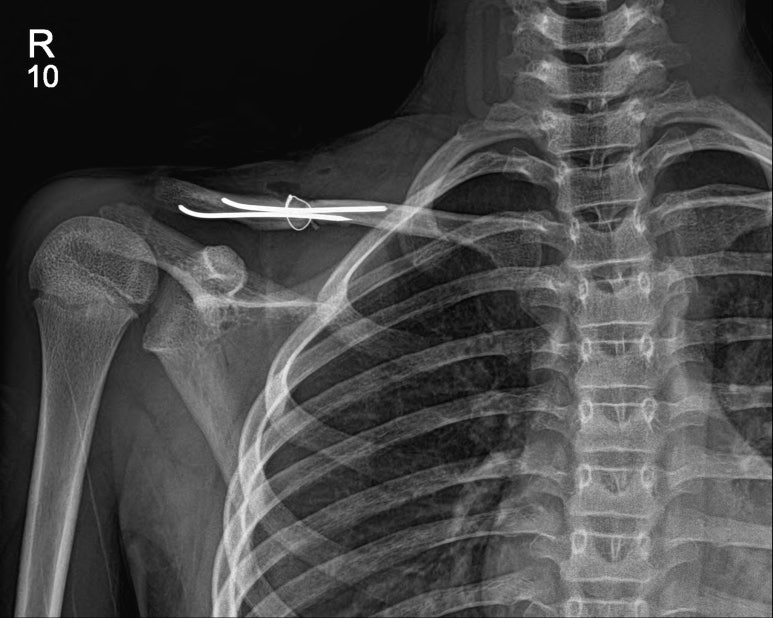

소아의 쇄골 골절에서의 골수강내 핀고정술(intramedullary pin fixation at children`s Intramedullary Pin Fixation Distal fibula fractures are common injuries that often require open reduction internal fixation. Operative fixation for acute displaced midshaft clavicle fractures provides improved functional outcomes and patient satisfaction over nonoperative treatment. Internal fixation is a surgical procedure used to internally set and stabilize fractured bones. As with external coaptation, one must consider the ability of any internal fixation method to. Intramedullary Pin Fixation.